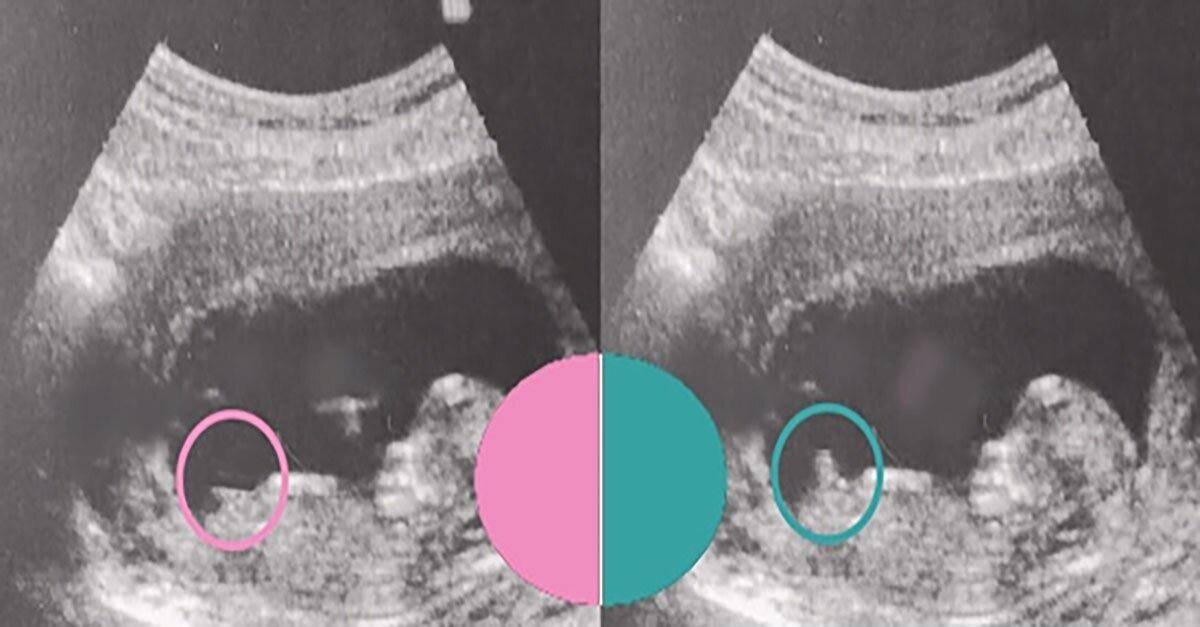

Через неделю после первого скрининга я решила провести расследование. 🫥 Раньше я думала, что не хочу знать пол до родов, но меня распирало с первой минуты, как я узнала о беременности! 😄 Многим предполагают пол малыша на первом скрининге, делают это по половому бугорку. Мне не предположили, поэтому пошла гадать сама и сравнивать узи знакомых мамочек) У кого было видно бугорок, у всех совпало. 1 фото - Определение 2 фото - узи с Лизой 3 фото - 1 скрининг сейчас Кого видите? У вас совпало?

Многим предполагают пол малыша на первом скрининге, делают это по половому бугорку.

Мне не предположили, поэтому пошла гадать сама и сравнивать узи знакомых мамочек) У кого было видно бугорок, у всех совпало.

1 фото - Определение